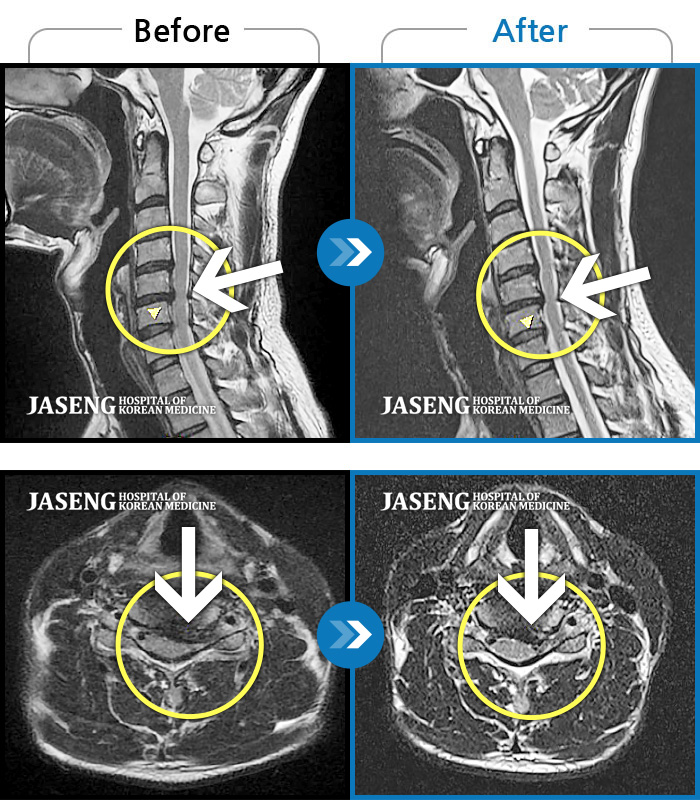

목디스크

광주 · 장영우 원장

후경부 양측부터 승모근까지 묵직한 통증, 좌측 상지 수지까지 이어지는 저린감

촬영시기

2121.04.27 ~ 2121.12.11

2021.12.17